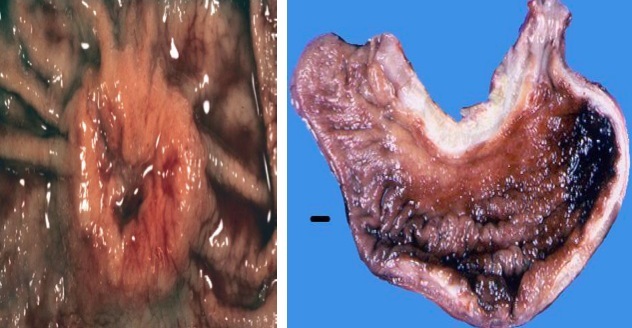

Gastric adenocarcinoma

* Pyloric outlet obstruction * C&C * **Krukenberg tumor; assoc w diffuse type** * Virchow lymph node: L. supraclavicular node * **Sister Mary Joseph nodule:** palpable nodule bulging **peri-umbilical** as a result of metastasis * Prognosis depends upon depth of invasion and nodal status

Intestinal type (LEFT IMAGE)

Diffuse type (RIGHT IMAGE)